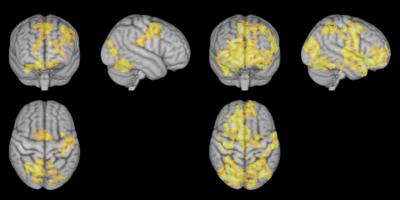

Nondirective meditation led to higher activity than during rest in the part of the brain dedicated to processing self-related thoughts and feelings. When test subjects performed concentrative meditation, the activity in this part of the brain was almost the same as when they were just resting.

"I was surprised that the activity of the brain was greatest when the person's thoughts wandered freely on their own, rather than when the brain worked to be more strongly focused," said Xu. "When the subjects stopped doing a specific task and were not really doing anything special, there was an increase in activity in the area of the brain where we process thoughts and feelings. It is described as a kind of resting network. And it was this area that was most active during nondirective meditation."

"The study indicates that nondirective meditation allows for more room to process memories and emotions than during concentrated meditation," says Svend Davanger, a neuroscientist at the University of Oslo, and co-author of the study.

"This area of the brain has its highest activity when we rest. It represents a kind of basic operating system, a resting network that takes over when external tasks do not require our attention. It is remarkable that a mental task like nondirective meditation results in even higher activity in this network than regular rest," says Davanger.